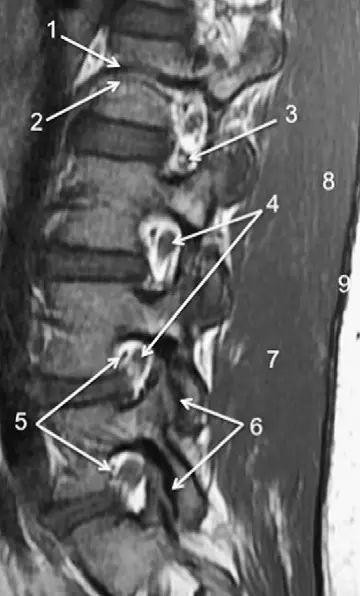

图1正常脊椎的MRI检查,左图为正中矢状位T2WI,右图为T1WI